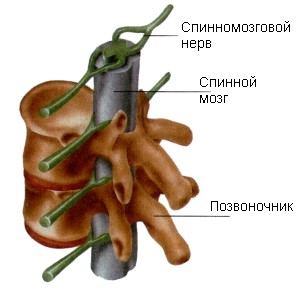

Расположение спинного мозга в спинномозговом канале позвоночника

Спинной мозг находится в позвоночном канале. Собой он представляет цилиндрический тяж диаметром примерно один сантиметр. Вверху спинной мозг переходит в головной, оканчивается внизу на уровне второго поясничного позвонка пучком нервов, отходящих от него, которые напоминают конский хвост. На рисунке вы видите, как выглядит спиной мозг

Рис. 2. Спиной мозг.